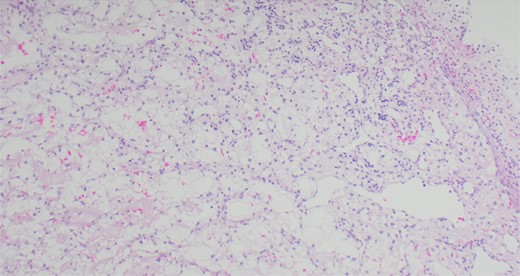

A 63-year-old male with a medical history of hypertension and progressive dyspnoea on exertion, underwent a computed tomography (CT) angiogram for the workup of a pulmonary embolism. There was an incidental finding of a 12-cm left renal neoplasm (Fig. 1), extensive metastatic nodal abdominal disease and bilateral metastatic pulmonary disease (T3 N2 M1). He was discussed at the Urology multidisciplinary team meeting (MDT) and commenced on Sunitnib, given the dissemination of disease. Repeat imaging showed a significant reduction in size of the pulmonary metastasis. Following which, he underwent a cryo-reductive nephrectomy that confirmed a clear cell RCC 102 mm, Grade 3. Development of a tongue lesion after a year warranted Otorhinolaryngology input. Clinical assessment with flexible nasendoscopy depicted a 0.5 cm by 0.5 cm pedunculated lesion on the midline of the tongue (Fig. 2). A biopsy under local anaesthetic confirmed a clear cell RCC (Fig. 3) that was positive for AE1/AE3, Vimentin (Fig. 4) and EMA. Further CT imaging, 1 month after the biopsy confirmed left hilar nodule progression from 2.3 to 3 cm. The medical oncology MDT recommended commencing Nivolumab. Following recurrent bleeding from the tongue, radiation to the area was determined to be the best treatment modality. The patient is still clinically well and tolerating oral intake with no significant large bleeds to date. Regular medical oncology, radiation oncology, urology and Otorhinolaryngology follow-up is ongoing, however, the prognosis is poor with such disseminated disease and the primary focus is on minimising morbidity.

Immunohistochemical staining confirming Vimentin positivity and the presence of malignant RCC over a benign Oncoytoma.